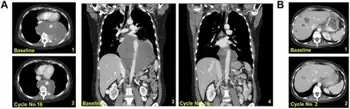

a) Recurrent metastatic myxoid liposarcoma, axial 1,2 and coronal 3,4 cuts show a partial response after 16 cycles of trabectedin b) recurrent poorly differentiated leiomyosarcoma, paired axial 1,2 cuts show a partial response with 2 cycles of trabectedin